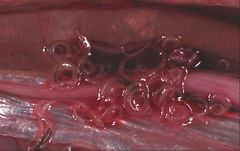

صفريات (باللاتينية: Ascaridida) رتبة تضم العديد من عائلات الديدان الأسطوانية الطفيلية ثلاثية الشفاه في نهايتها الأمامية. They were formerly placed in the subclass Rhabditia by some, but morphological and DNA sequence data rather unequivocally assign them to the Spiruria. The Oxyurida and Rhigonematida are occasionally placed in the Ascaridida as superfamily Oxyuroidea, but while they seem indeed to be Spiruria, they are not as close to Ascaris as such a treatment would place them.[1] These "worms" contain a number of important parasites of humans and domestic animals.

- The Anisakidae are also called the "marine mammal ascarids". The larvae of these worms cause anisakiasis when ingested by humans in raw or insufficiently cooked fish, but do not reproduce in humans.